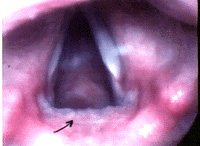

The photograph to the right shows inflammation due to reflux (at the arrow). The white bands forming the inverted "V" are the vocal folds. The posterior portion of the opening into the windpipe (called the posterior glottis) is thickened, due to acid irritation.

Physical examination requires a careful examination of the larynx. The most common site of inflammation is the back of the larynx. This is the first site where refluxed acid comes in contact with the throat. The lining of the throat becomes inflamed, which is seen as increased redness and swelling. The vocal folds themselves may also be swollen.